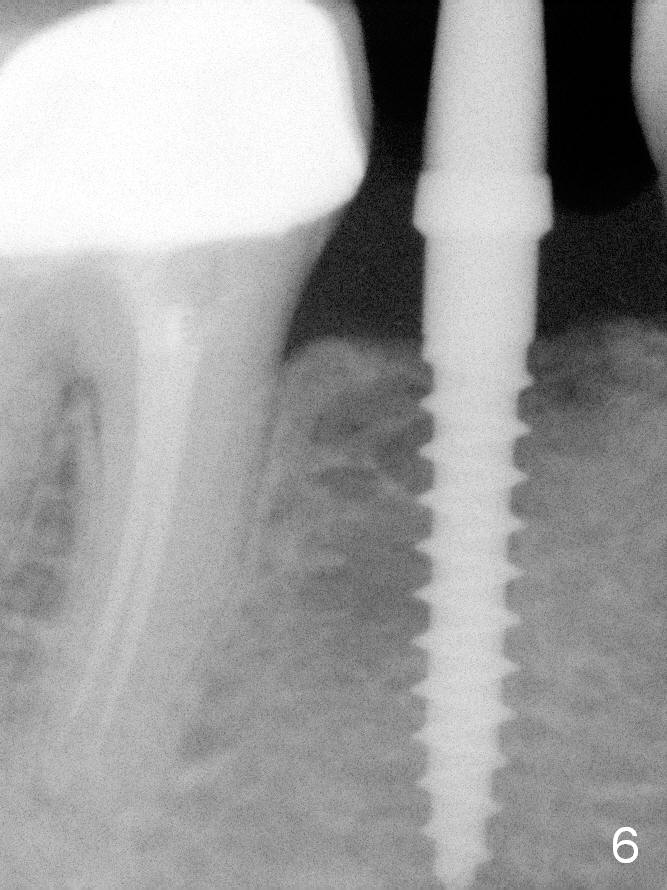

A 2.5x12(2) mm 1-piece implant is placed (Fig.6). There is mild bone loss distal 4 months postop (Fig.8 * (possible artifact due to angulation)). No continuous bone loss 15 months post cementation (Fig.9). There is mild bone resorption mesially 2 years 3 months post cementation (Fig.10).